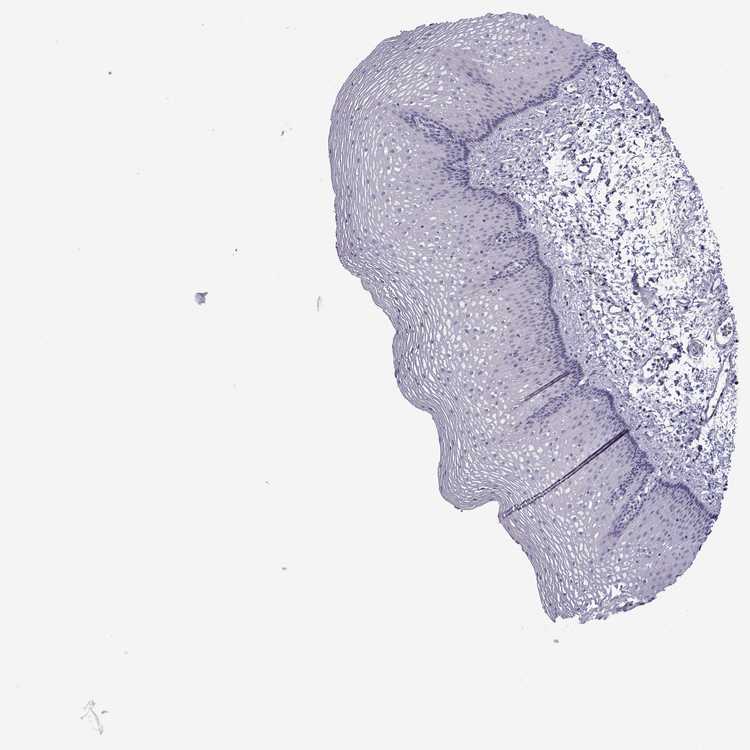

ESOPHAGUS - Antibody stainingi

Antibody staining in the annotated cell types in the current human tissue is reported as not detected, low, medium, or high, based on conventional immunohistochemistry profiling in selected tissues. This score is based on the combination of the staining intensity and fraction of stained cells.

Each image is clickable and will lead to virtual microscopy that enables deeper exploration of all samples and also displays staining intensity scores, fraction scores and subcellular localization as well as patient and tissue information for each sample.

Antibody HPA048349

Squamous epithelial cells Not detected